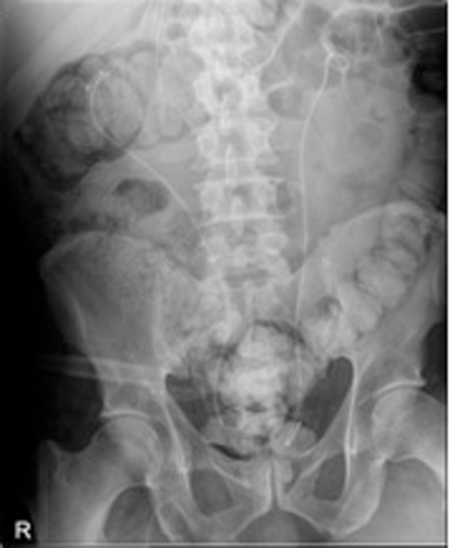

Case 2

Image 1.

- What do these X-Ray KUB films show?

Image 1: Ureteric stent with stone formation in the bladder, mid ureter and renal pelvis. A left upper calyceal renal calculus.